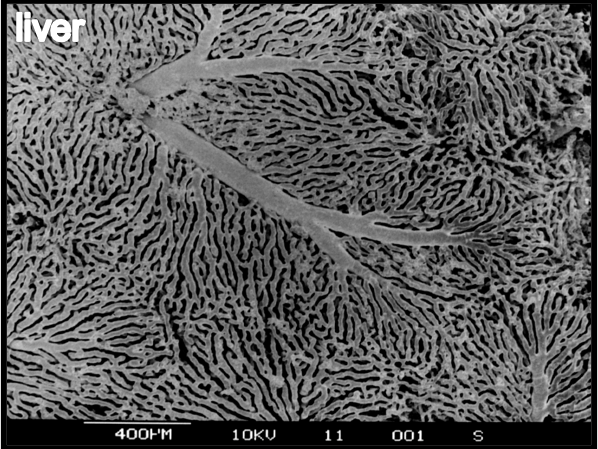

Colon mucosa

Anaglyphic 3D SEM image of microvascular corrosion cast shows normal colonic vasculature in the gut.